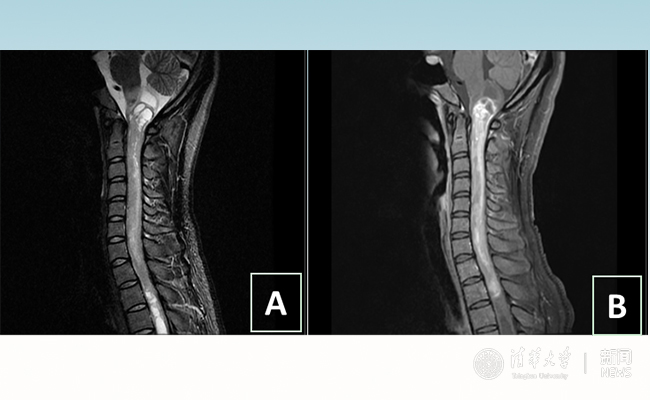

2018.01拯救“90后”女孩 清华长庚神经外科切除20多公分髓内肿瘤

“愿得韶华刹那,开得满树芳华。”27岁的患者小甜(化名)在星空体育附属北京清华长庚医院成功进行了手术,神经外科主任王贵怀为其切除了自延髓至胸髓的长达20余公分的脊髓内肿瘤。1月9日,小甜顺利出院,再续芳华!